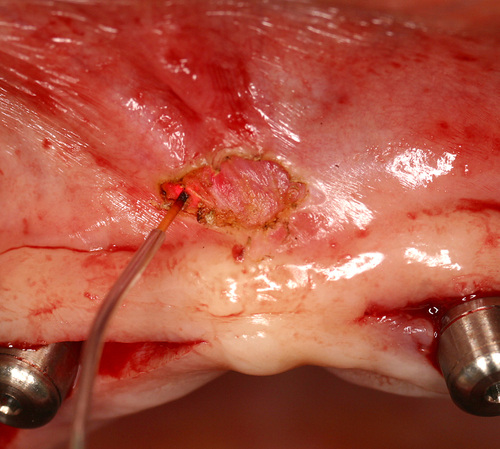

Les frénectomies, par exemple, sont effectuées sans aucun saignement et sans point de suture (fig.23)

Fig. 23

Frénectomie labiale effectuée avec un laser Diode